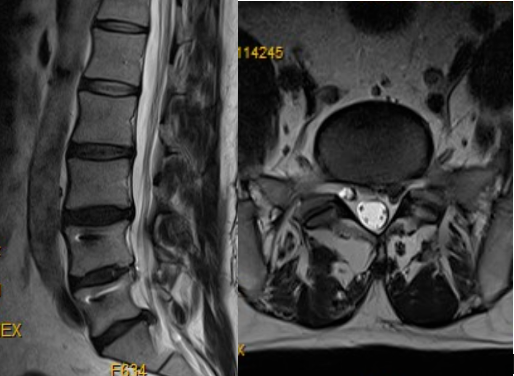

患者董某,51岁;有L4-5椎间盘摘除+椎间植骨融合内固定手术史。本次入院经影像学辅助检查,显示患者腰椎L2-3、L3-4椎间盘膨出,L5-S1椎间盘突出,左侧神经根受压迫。白登彦主任团队结合专科查体确定患者症状责任阶段,并综合评价患者年龄、手术适应症、手术史等多方面因素,为患者制定了L5-S1节段脊柱内镜辅助下突出椎间盘切除联合纤维环缝合手术治疗方案。术后患者恢复良好,对疗效满意。

(患者术前影像资料)